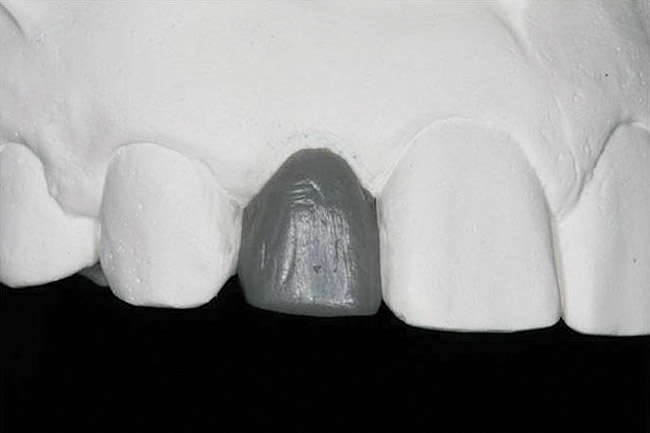

Figure 21   Gingival zenith planning: The location of the gingival zenith for this missing lateral incisor is not fully evident during initial clinical evaluation (Fig 21). Subsequent diagnostic waxing reveals the position of the planned gingival zenith (Fig 22). A thermoplastic template captures the position of the zenith and enables transferring this location to the clinical environment (Fig 23 and Fig 24). Final crown contours are defined by soft-tissue form (Fig 25).

Figure 21

Figure 22  Gingival zenith planning: The location of the gingival zenith for this missing lateral incisor is not fully evident during initial clinical evaluation (Fig 21). Subsequent diagnostic waxing reveals the position of the planned gingival zenith (Fig 22). A thermoplastic template captures the position of the zenith and enables transferring this location to the clinical environment (Fig 23 and Fig 24). Final crown contours are defined by soft-tissue form (Fig 25).

Figure 22